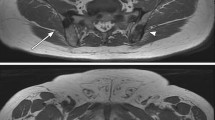

MRI examination

The MRI was performed on a 1.5-T Avanto (Siemens Healthcare), and included the following sequences: sagittal T1w of the spine and pelvis, axial diffusion-weighted imaging (DWI) using b1000 s/mm2 of the spine and pelvis, sagittal short tau inversion recovery (STIR) of the spine (Table 1). A 3D maximum intensity projection (MIP) was constructed from the b1000 s/mm2 images. Figure 2 demonstrates an example of whole-body MRI.

Bone metastases were found in 8% (95% CI: 4–14, 13 out of 161), of which 23% (95% CI: 5–67, 3 out of 13) had less than four metastases. In one patient, a solitary metastasis was found in the 9th thoracic vertebra, but a biopsy from the lesion showed chronic lymphatic leukemia (Fig. 2). The remaining 7% (95% CI: 4–13, 12 out of 161) were treated clinically as if they had metastases from prostate cancer without a confirmatory biopsy. The prevalence of metastases in high-risk patients was 10% (95% CI: 5–17), and 83% (10 out of 12) were found in patients with Gleason grade group ≥ 4. The remaining metastases were found in two patients who did not undergo a confirmatory prostate biopsy. The pelvis was affected exclusively in 4 patients, and both the spine and pelvis were affected in the remaining 8. No patients demonstrated metastases in the spine without concomitant metastases in the pelvis (Fig. 3).

A 56-year-old patient with PSA 33 ng/ml and Gleason grade group 4. The white whole arrows indicate a bone metastasis in the right ischial tuberosity, while the stippled arrows indicate enlarged retroperitoneal lymph node. a Coronal 3D MIP based on DWI b1000 s/mm2. b Axial T1w. c Axial DWI b1000 s/mm2. d Axial DWI b1000 s/mm2. e axial T1w